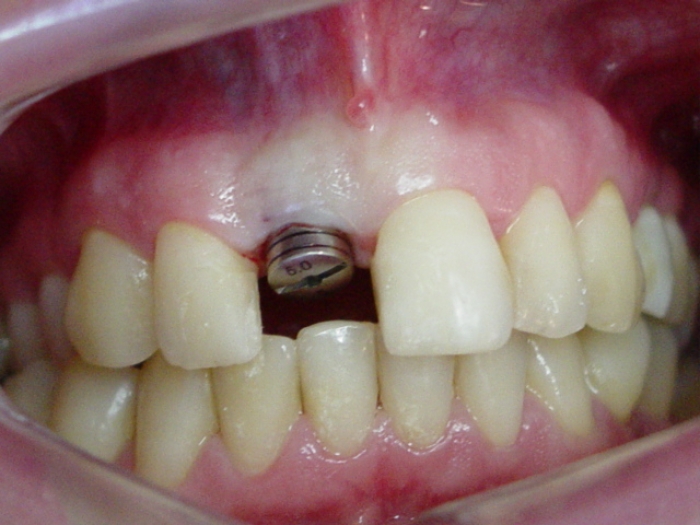

Imagem de um implante com cicatrizador e com o dente provisório removido.